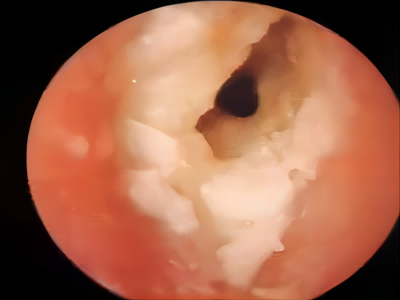

外耳道炎外耳道结黄痂图

外耳道炎在检查时显示有很多黄色分泌物,附着在外耳道黏膜壁上,脓痂上还有白色豆腐渣状的鳞屑堆积,患者自觉耳痛、瘙痒、耳道潮湿。